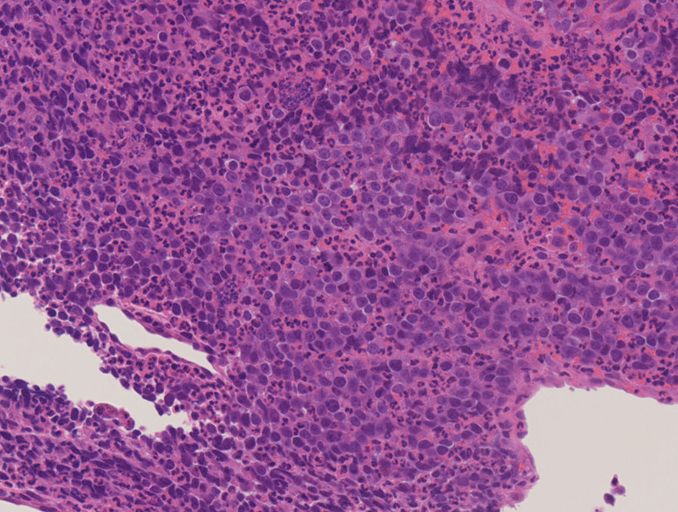

IWT case: 30歳代半ば,女性; 喫煙歴:15本/日,20歳から現在まで

当院を受診する4か月前から前胸部違和感を自覚していた. 2か月前から喘鳴を伴う咳嗽があり近医を受診.気管支喘息が疑われ加療されたが症状は改善しなかった.

経過観察中に施行された胸部CTでは左肺癌が疑われた.精査加療目的に当院呼吸器内科を紹介受診.

血液検査:腫瘍マーカー cytokeratin 19の上昇あり[14 (>3.5ng/mL)],ProGRP, CEA, CA19-9の上昇なし

CT画像:左肺から縦隔に及ぶ腫瘍(肺は単独病変. 肺内転移なし.),乳腺腫瘤,子宮腫瘤, 多発肝腫瘤あり.

処置: 気管支内視鏡検査で,1.左肺腫瘍からTBB (VS1),2.腫瘍と一塊になったリンパ節からEBUS-TBNA (VS2),を施行された.

CT画像および肺腫瘤生検組織